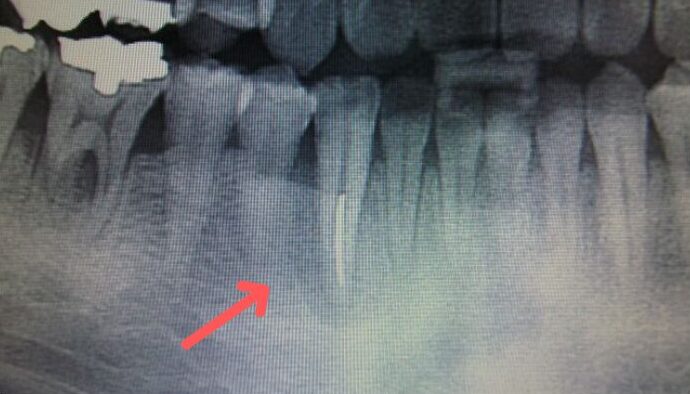

■初診時の状態

対象の歯は感染が進行して、歯の根の先や周囲の骨が失われている状態でした。

一般的には抜歯と診断される可能性もあるケースです。

■ 診査・治療

診査の結果、噛み合わせと歯周病と歯髄に問題があることがわかりました。

根の治療とかみ合わせの調整を行い、歯周病治療を行いました。